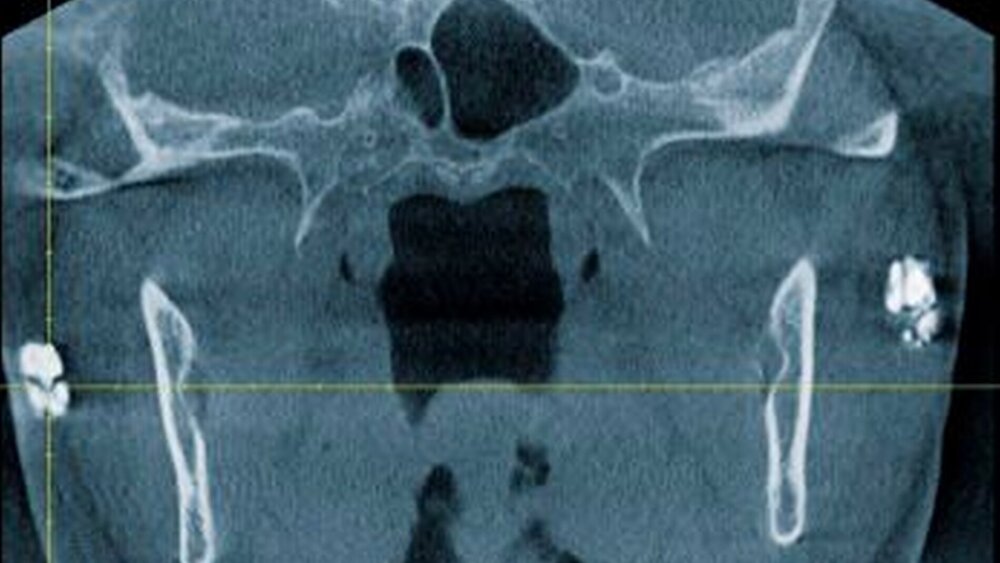

Zur genauen räumlichen Zuordnung der Verschattungen unterhalb der Incisurae semilunares wurde eine dentale digitale volumentomografische Untersuchung durchgeführt (Abbildungen 2 bis 4).

Für die Darstellung von Lymphknoten oder Speichelsteinen stellt die Sonografie die Methode der Wahl dar. In der Regel ist keine Abgrenzung zu weichgeweblichen Strukturen möglich. Dies muss bei kalzifizierenden Metastasen oder hartgewebebildenden Neoplasien (wie Osteosarkome) berücksichtigt werden. Um eine eindeutige Zuordnung zu den umgebenden Weichgewebe-strukturen gewährleisten zu können, sollte eine 3-D-Summationsaufnahme (DVT, CT) durchgeführt werden.